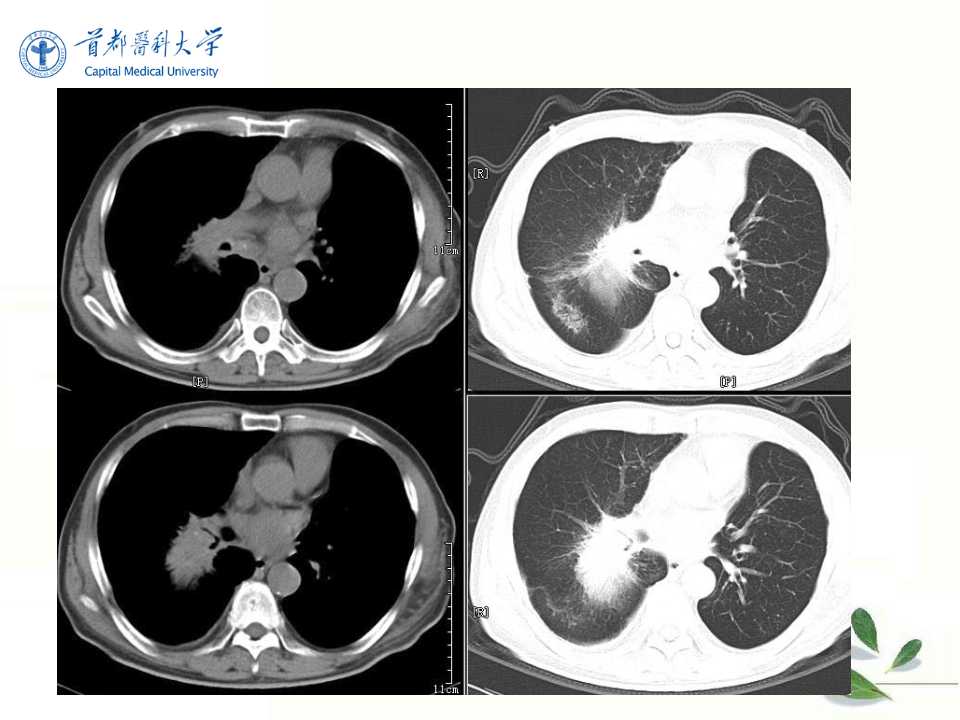

肺癌的影像学检查